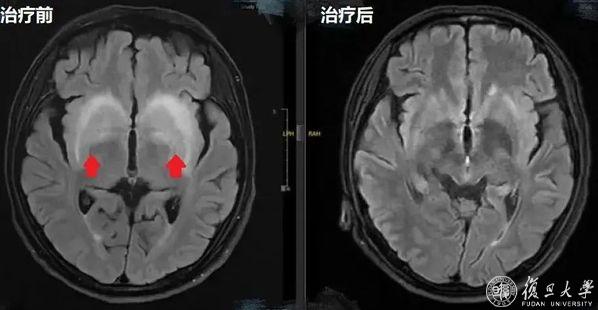

【两次头颅MR对比】红色箭头指示病灶

经过十几天的综合治疗,李先生不仅恢复了意识,肢体抽搐的症状也消失了,精神越来越好。复查头颅磁共振显示“双侧基底节对称高信号较前好转”,随访心功能等较入院时也有了明显改善。